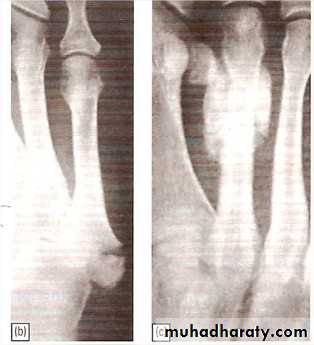

Avulsion of base of fifth metatarsal

Result from forefoot inversion injury.

Base of 5th MT avulsed by peroneus brevis tendon.

Treatment: Below knee walking cast for 3wks.